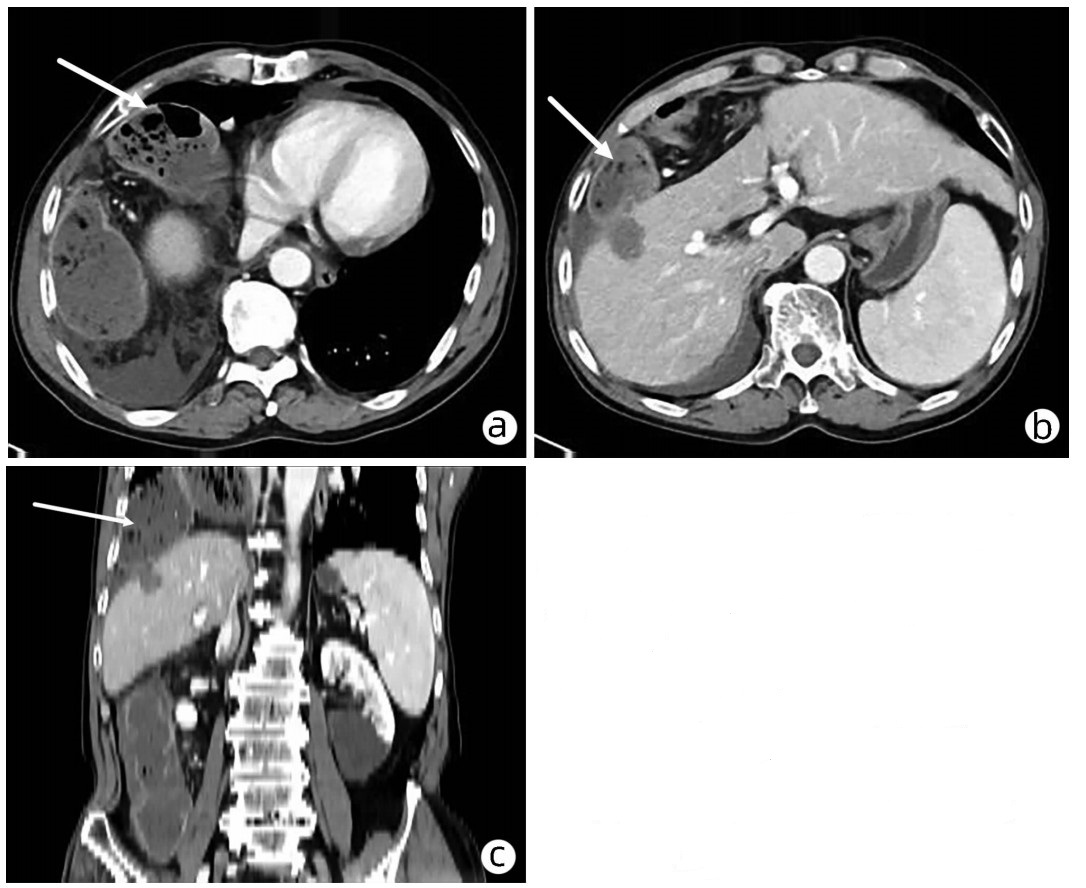

Hepatocellular carcinoma with bile duct tumor thrombus: A case report

Renjie LU, Fangfang SUN, Jie DU, Lirong ZHAO

2022, 38(8): 1872-1874. DOI: 10.3969/j.issn.1001-5256.2022.08.028

Abstract(831) HTML (461) PDF (3665KB)(88)